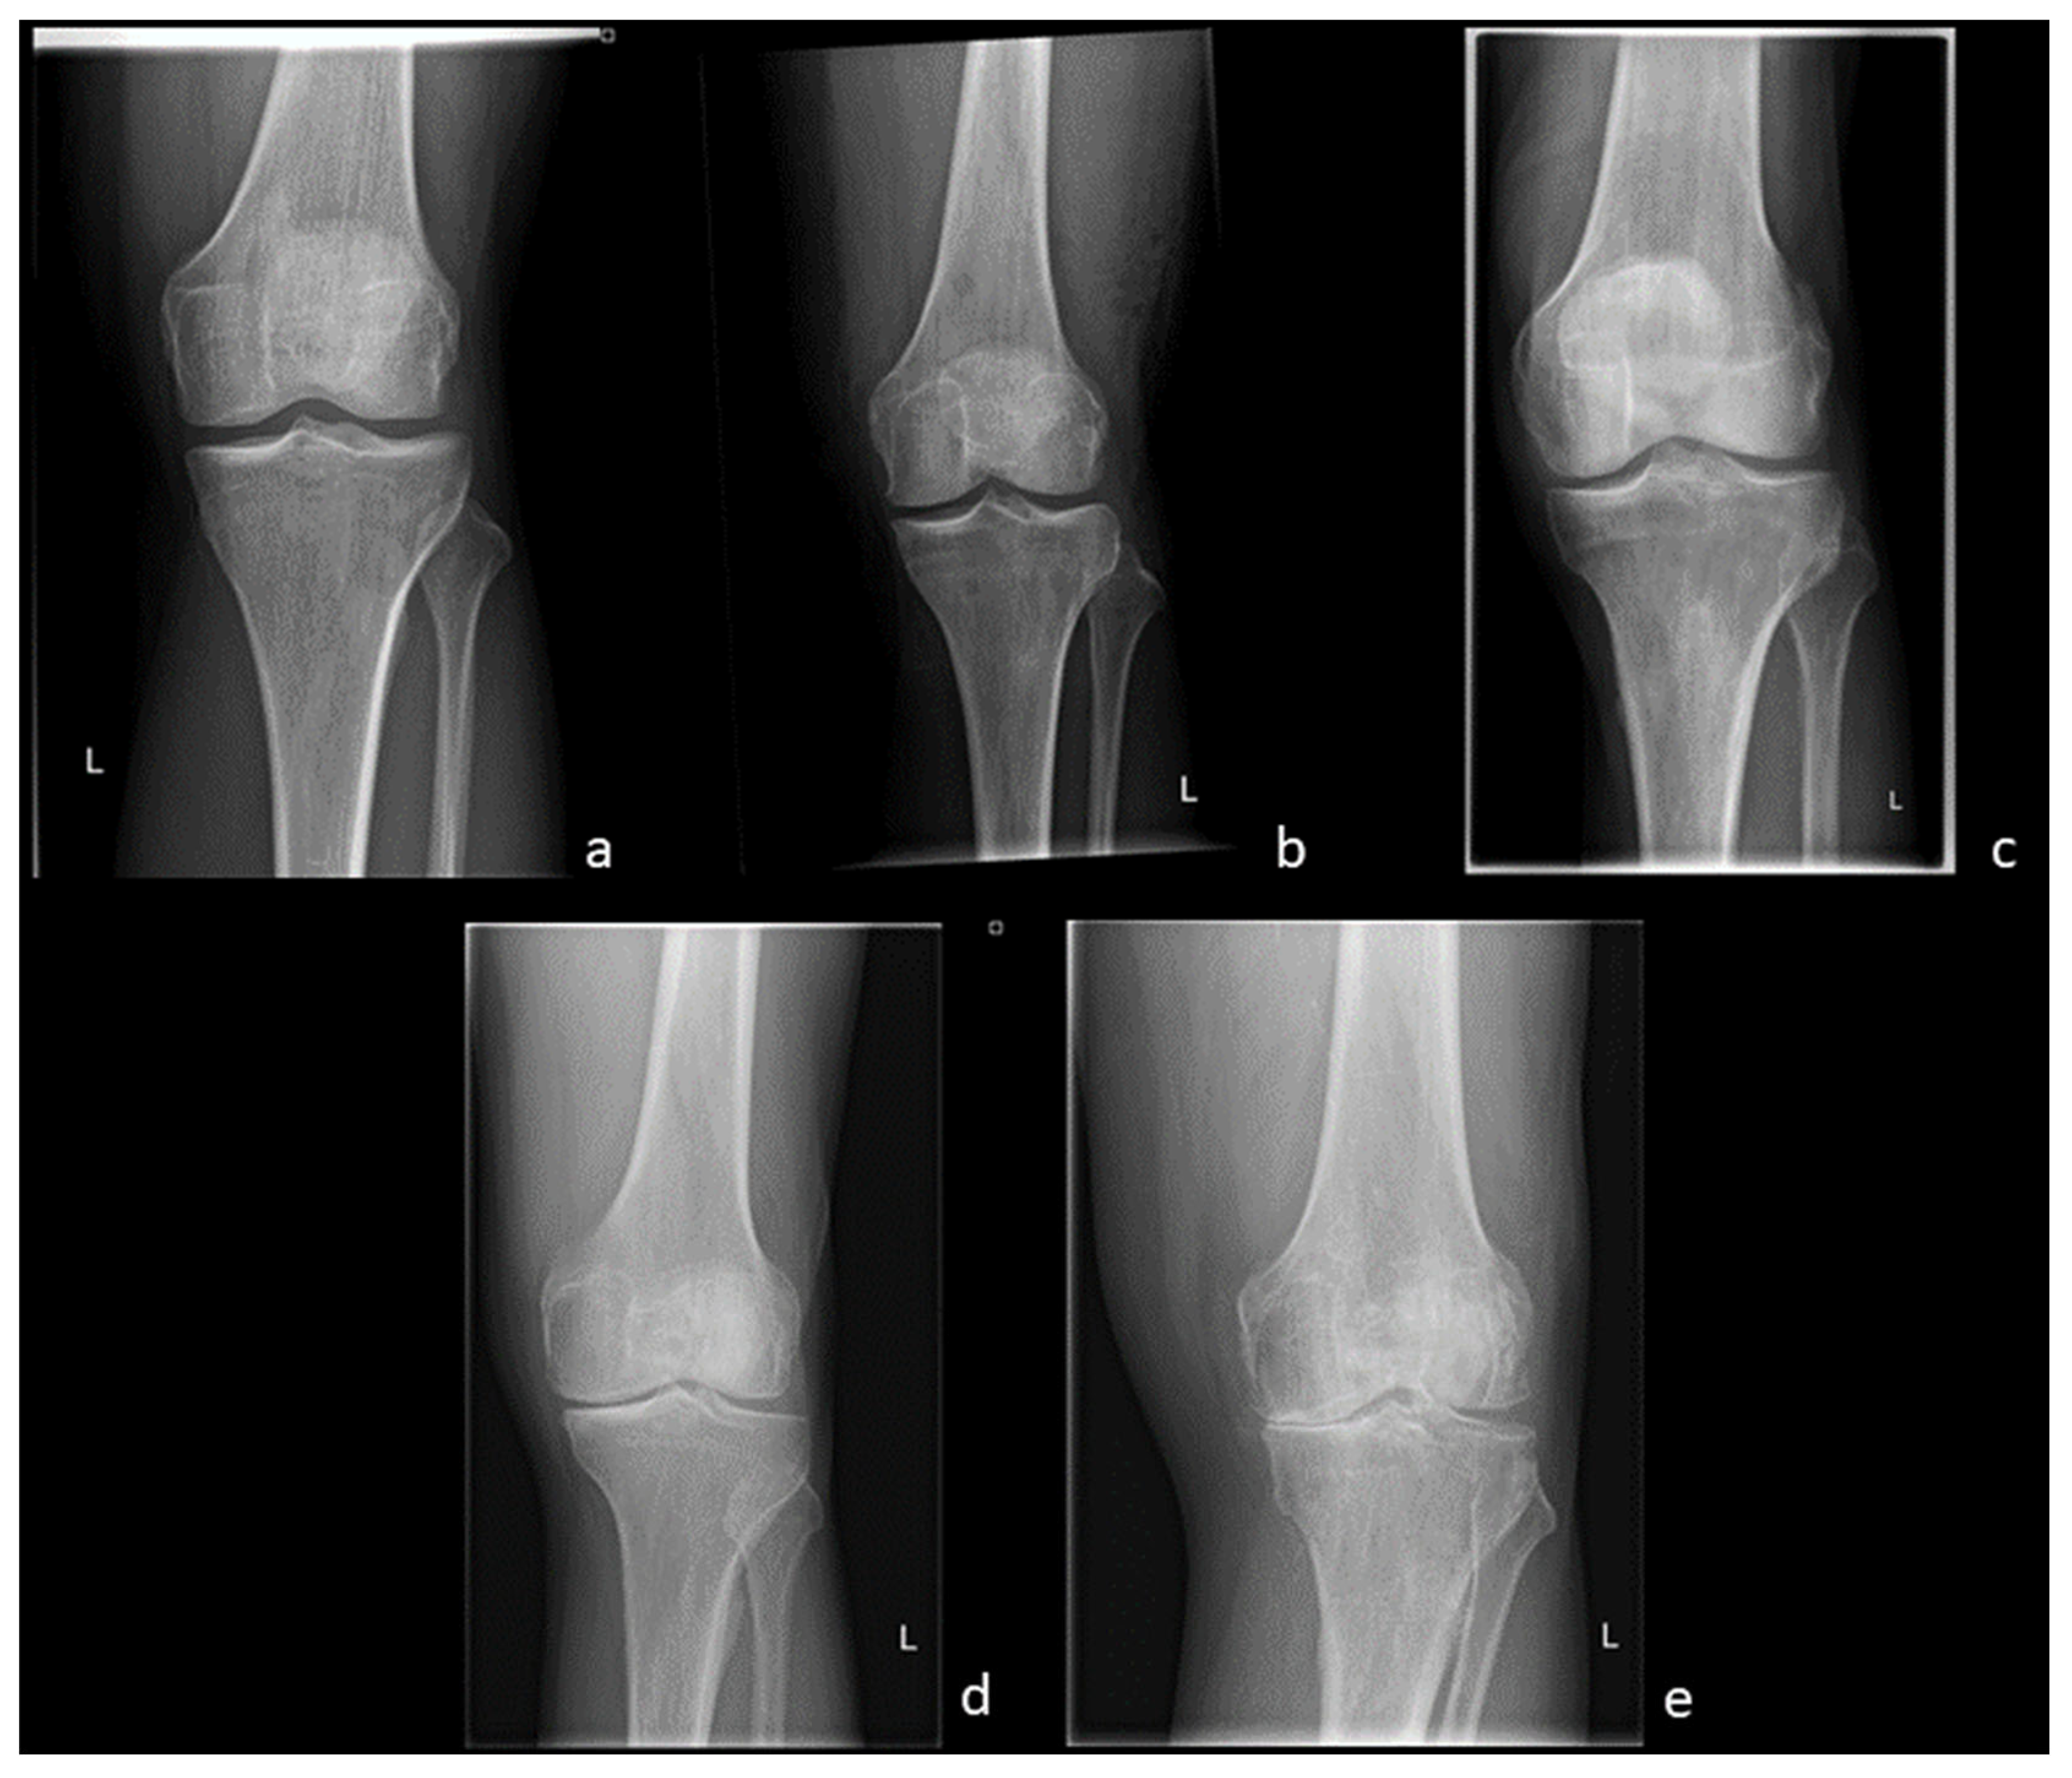

Radiography, which is still the most commonly used imaging technique for OA, is usually acquired in two planes, i.e., the lateral and anterior-posterior view. It is widely available and inexpensive. In addition, weight-bearing images can be obtained [27]. Depending on the clinical facility and the clinical patient history, additional views, such as the patella view or the Rosenberg view, can be obtained to evaluate specific regions of the joint. Introduced by Kellgren and Lawrence in 1957, the grading of OA is still conducted on a four-grade scale (Figure 1). Grade 0 indicates the absence of OA-specific changes in the joint, Grade I is defined as doubtful OA-changes, and Grades II and III refer to minimal and moderate changes, respectively, and can be distinguished by the presence or absence of subchondral sclerosis. Finally, Grade IV considers severe stages of OA associated with joint deformity and severely reduced joint space width (JSW) [28].

Figure 1. OA Stages (Kellgren and Lawrence, 1957)—(a) Grade 0: Physiological joint. (b) Grade I: Subtle JSN in the medial compartment with osteophytic lipping. (c) Grade II: Definite JSN in the medial compartment. (d) Grade III: Definite JSN in the medial compartment and sclerosis of the subchondral bone. (e) Grade IV: JSN with a bone-on-bone phenomenon and deformity of the medial tibial plateau as well as the medial femoral condyle.